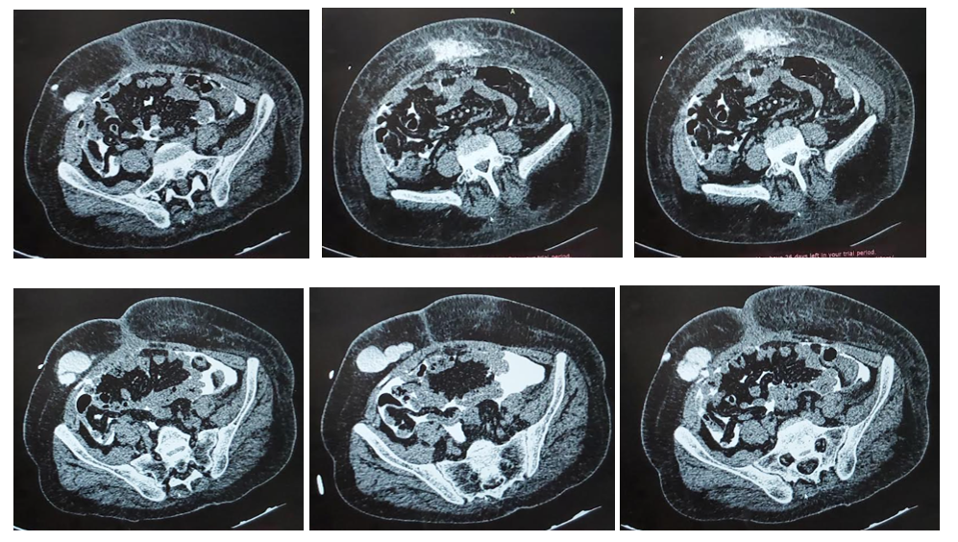

Four months after the start of exchanges, the patient presented with abdominal distension with loss of ultrafiltration (Figure 1.A). Clinical examination revealed a distended, soft, asymmetric abdomen, with a palpable, painless left lateral mass opposite the old left laparoscopic scar, with no leakage at the current emergence site on the right. Intraperitoneal pressure was elevated to 22cmH2O.

Figure 1.

The evolution was favorable after one week, with progressive regression of the left abdominal infiltration (Figure 1.B).

The patient was seen in consultation three months after the change to the PD program. He was clinically euvolemic, in good general condition, with systolic blood pressure at 120 mmHg and diastolic at 70 mmHg, and stable weight. A mean daily ultrafiltration of 1 l, good purification quality with KT/V at 1.3, weekly creatinine clearance at 51 liters per week per square meter, with no hydroelectrolytic disorders and improved left abdominal infiltration (Figure 1.C).